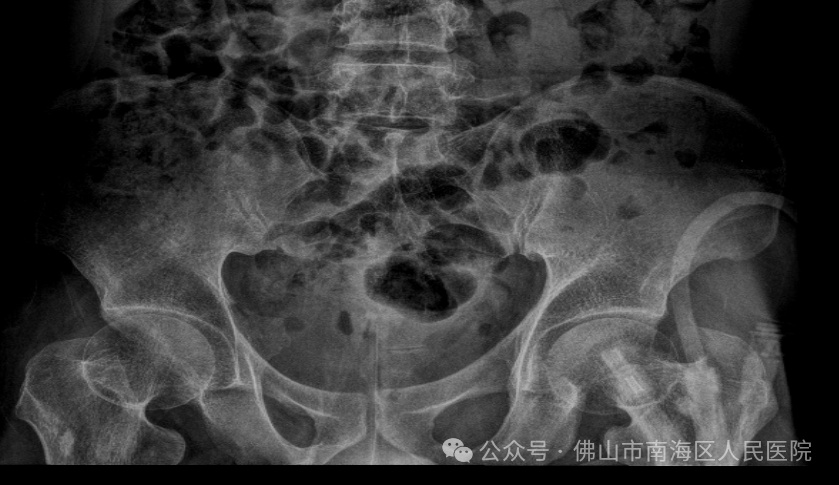

入院后经CT检查,发现小王膀胱有大量结石。

考虑患者结石数量较多、较大,手术方式选择膀胱开刀4cm取石。

开刀后,映入眼帘的是,密密麻麻粘连在一起的“结石群”,最大的有4cm,一共49块,约3斤重!